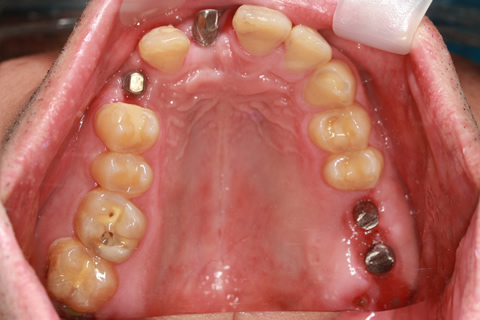

症例1

- 年齢・性別

- 55歳女性

- 治療期間

- 2ヶ月

- 抜歯

- なし

- 治療費

- 66万円

- 備考

- 右下6.7欠損

- 治療内容

- 右下6.7欠損部にインプラント埋入

- 施術の副作用(リスク)

- オペによる知覚障害。インプラントによる歯肉炎。インプラント脱落。